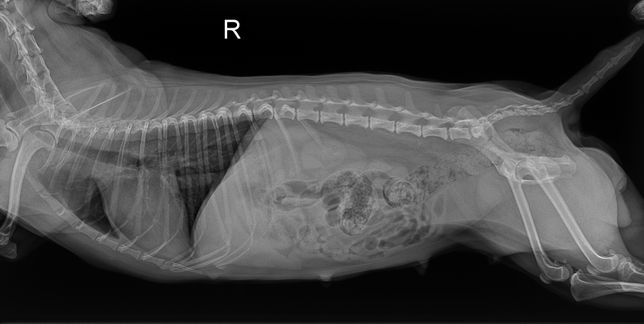

- 반려동물 건강반려동물Q. 강아지 엑스레이 사진 좀 봐주실 수 있는 분8살 암컷 강아지이고 어제 유선종양이랑 중성화 수술했는데 수술 전에 찍은 엑스레이에서 궁금한 점이 생겨 물어봅니다 혹시 엑스레이 상에서 제가 빨간색으로 동그라미 친 부분이 뭔 지 알 수 있을까요? 정확하게능 아니더라도 가늠이라던지 한번만 봐주세요..

- 반려동물 건강반려동물Q. 강아지 엑스레이 사진 좀 봐주세요ㅠㅠ강아지 엑스레이 찍었는데 빨간색 동그라미 친게 종양일까요? 유선종양 수술했는데 저 액스레이에 하얀게 뭔지 설명을 못 들었네요 아시는 분 계신가요?